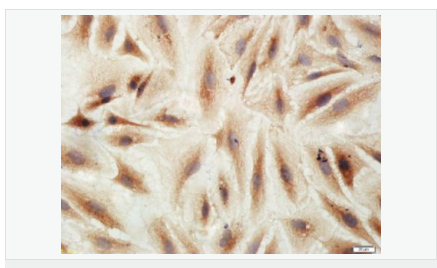

產(chǎn)品應(yīng)用WB=1:500-2000 IHC-P=1:100-500 IHC-F=1:100-500 Flow-Cyt=3ug/test ICC=1:100-500 IF=1:100-500 (石蠟切片需做抗原修復(fù))

image.png